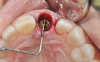

Recognizing that achieving primary stability in extraction sites is more challenging than in healed ones, the use of tapered implants may be considered to achieve better primary stability for immediate implant placement. Kan and colleagues reported decreased rotational instability with tapered implants in immediate placement protocols.9 Utilizing an implant with well-defined threads that improve lateral bone engagement may improve stability (Figure 1 through Figure 4). Conceptually, it makes sense to use tapered implants or those with threads that cut and condense bone; however, there is little evidence in the literature supporting superior primary stability based on implant design.10 Although implant design may offer advantages, clinicians should focus more on site preparation and final drill selection as the keys to achieving adequate primary stability.

(3.) This series of clinical images illustrates the use of an implant with well-defi ned

threads that improve lateral bone engagement. In a multirooted extraction socket where there are large voids, this can help to achieve initial implant stability.

Figure 3